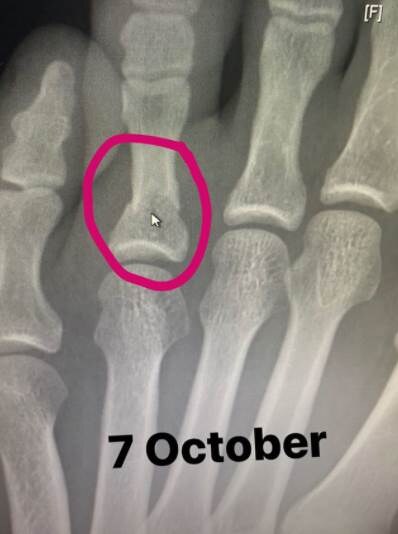

Habib je na svom Instagram "storiju" pokazao i rentgendski snimak slomljenog palca:

Na obe fotografije ispisan je datum – renten od 7. a otečeno stopalo od 8. oktobra. Meč je održan 24.

"Nakon svega što je taj dečko prošao u poslednje možemo biti srećni što smo imali priliku da ga gledamo večeras. Čuo sam da je pre tri nedelje slomio stopalo i to nikome nije rekao. Na stopalu ima slomljena dva prsta i jednu kost. On je jedno od najizdržljivijih ljudskih bića na planeti", ispričao je Vajt, koji je prvi otkrio novinarima o povredi.